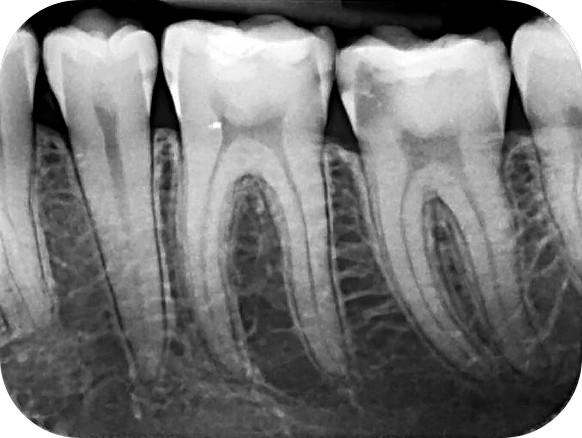

الأشعة داخل الفم

(Intraoral X-ray)

لتشخيص التسوس، وفحص العصب، وكشف أي تلف داخلي في الأسنان.